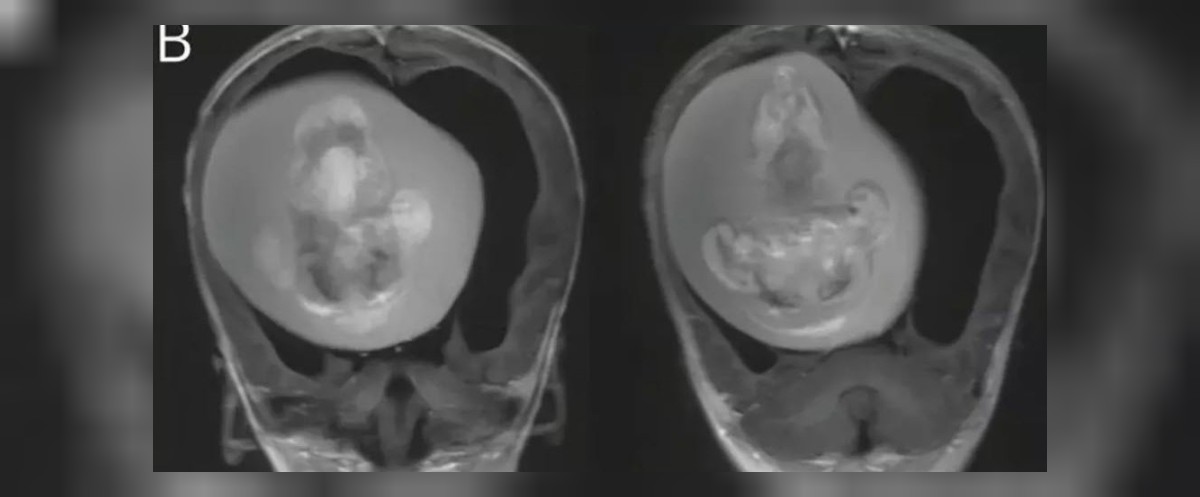

Vaka raporuna göre, bebeğin beyninde sıvı birikmesi ve basınç artışı olduğu görüldü. Daha detaylı incelemeler sonucunda, bebeğin anne karnındayken bir ikiz kardeşi olduğu ama ikinci bebeğin yeterince gelişemediği ve kardeşinin kafatasının içine gömüldüğü ortaya çıktı.

Doktorlar, fetüsün üst vücut kısımlarının, kemiklerinin ve hatta tırnaklarının oluştuğunu, rahimdeki kardeşinin içinde kaldığı süre boyunca büyümeye devam ettiğini belirtti.